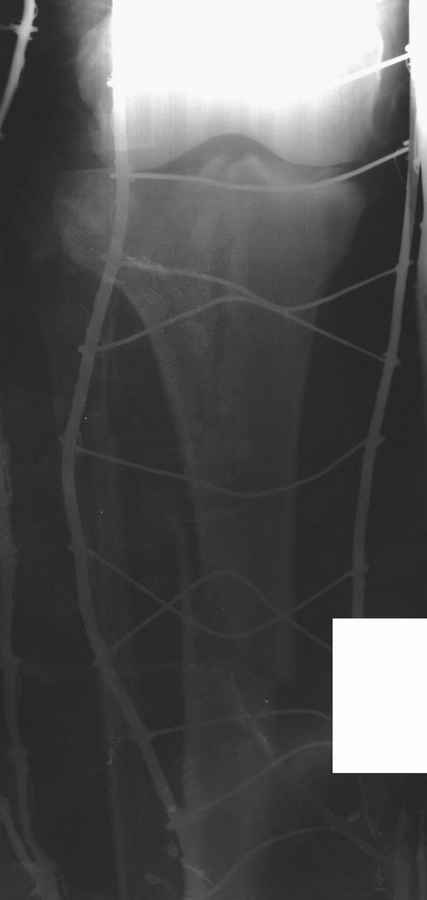

"Плотный отек и кровеизлияние" результат осевших мыщелков и уменьшения высоты конечности. Кондиции мягкой ткани в данном этапе не позволяет без риска делать операцию. Если у больного отсутствует вытяжение, тогда для улучшения состоянии мягкой ткани и для дистракции надо установить любой мостовидный наружный фиксатор от бедра к голени. Больной получит свободу, будеть передвигаться с помощью костылей и тогда сделайте нужные исследования включая Компьютерную Томограмму.

После утихания отеков и образования "wrinkle sign" сделать операцию на тибиал плато. Вариант длинная пластина с латеральной стороны. Надо приподнять импрессию с ауто или синтетическим графтом. Учитывая перелом медиального мыщелка antiglade пластина из минидоступа медиально..

В своем арсенале все компании имеют длинные перкутанные пластины. Преимущества примерное как от гвоздя, открывается только латеральная стороны на уровне перелома тибиал плато, а в остальном перкутанный Jig Insertion Device.

Надеюсь, представленные снимки разных случаев помогут разобраться в тактике, и критика примется без личной обиды.